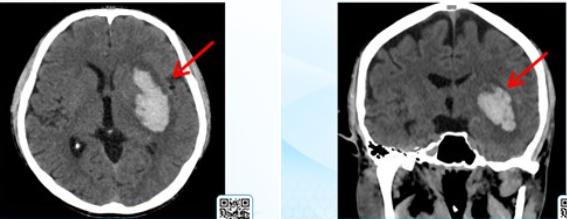

Tổn thương não trên phim chụp - Ảnh BVCC

Kết quả CT sọ não khẩn ghi nhận ổ xuất huyết lớn tại nhân bèo trái, kích thước khoảng 28 x 52 x 28 mm, kèm phù nề não đáng kể và đường giữa đã bắt đầu lệch sang phải.

Tuy nhiên, chỉ trong thời gian ngắn, dù đã hồi sức tích cực, tình trạng thần kinh vẫn xấu dần. CT kiểm tra lại cho thấy khối máu tụ tăng nhanh lên khoảng 37 x 63 x 32 mm, đẩy lệch đường giữa tới 15 mm, chèn ép não thất, tri giác tụt nhanh, người bệnh rơi vào hôn mê sâu.